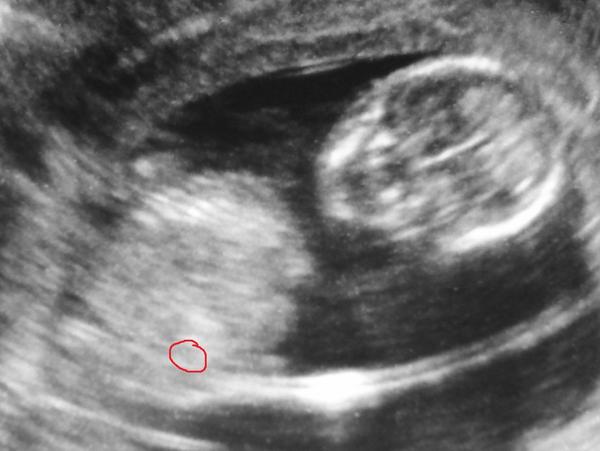

Nie je to až tak dôležité len ma to zaujma. Bola som u lekárky pred týždňom a robila mi ultrazvuk bol to zážitok lebo prvý krát bol aj priateľ. Povedala, že som v 13. týždni a všetko je ok, že pohlavie je skoro určiť a nič nevidí. Potom mi robila zdola ultrazvuk a tak sa pousmievala a ja, že čo nič tam nevidím. A ona, že sa to javí ako chlapec. Pozerala som si dnes jednu fotku neviem čo to je vyzerá to ako nohy a v strede niečo ako pipik, ale to je len akoby taká čiaročka ani sama neviem čo to je. Povedala, že mi to ale nevie povedať, že si to ešte len mysli a nie na 100 percent. Ja cítim dievčatko priznám sa mám už aj niaké dievčenské veci doma. Je pre mňa dôležite jeho zdravie a šťastie len ma to prekvapilo viac to, že to vôbec vypustila tak skoro. Ja verím svojmu citu, ale je vôbec možno tak skoro, aby tam niečo videla? Alebo kedy to bude isté rozoznať? Myslela som, že takto skoro sa to nedá. A sú aj skúsenosti, že sa pomýlia ako chlapček je baba a naopak? Má niekdo skúsenosti? diky. 🙂 A inak je to to najkrajšie čo v živote je mať to malé v brušku taký dar života 😉

Tak z téhle fotky to nikdo nepozná 😅